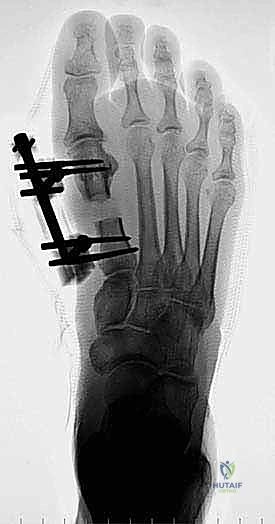

الخطوة الثالثة: قص العظم (Osteotomy)

باستخدام منشار جراحي ميكروسكوبي دقيق، يقوم الدكتور هطيف بقص عظم مشط القدم. تعتمد زاوية وشكل القص (مثل القص المائل أو القص على شكل حرف Z) على مقدار الإطالة المطلوبة وشكل العظم المتبقي من الجراحة السابقة.

الخطوة الخامسة: التثبيت الداخلي القوي (Internal Fixation)

لضمان التئام العظم في وضعه الجديد والطويل، يجب تثبيته بقوة شديدة. يستخدم الدكتور هطيف أحدث الشرائح المعدنية التيتانيوم ذات الزاوية الثابتة (Locking Plates) والمسامير الدقيقة. هذا التثبيت القوي يمنع أي حركة بين العظام ويسمح ببدء العلاج الطبيعي في وقت مبكر.

بعد التأكد من الطول المثالي واستقرار التثبيت باستخدام الأشعة السينية في غرفة العمليات، يتم غسل الجرح بمضادات حيوية وإغلاق طبقات الأنسجة والجلد بخياطة تجميلية دقيقة لتقليل الندبات قدر الإمكان. يتم وضع ضمادة ضاغطة وداعمة للقدم.